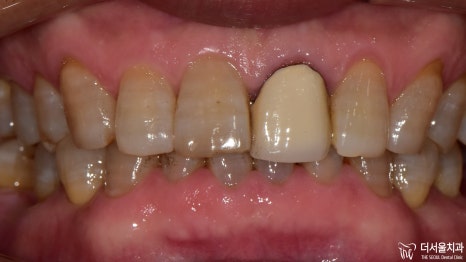

이제 결과를 보여드릴 차례네요.

모든 보철을 지르코니아를 사용하여

심미성을 한껏 더해주었습니다.

이렇게 몇 곳만 바뀌어도

가만히 있던 주변 치아들까지

좀 더 건강하고 활기차 보이지 않나요?